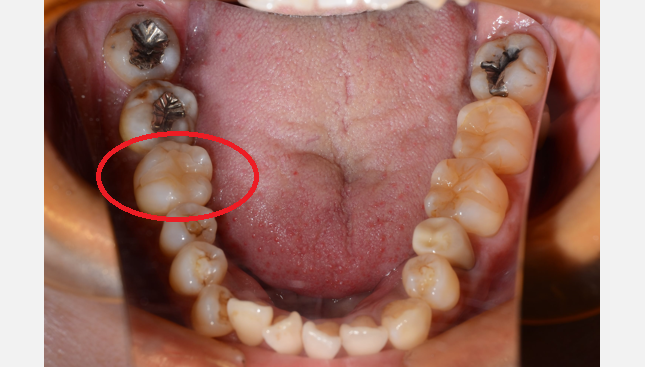

CASE2

| 年齢 ・ 性別 |

36歳・女性 |

|---|---|

| 主訴 | 虫歯を治したい 左下6番・左下7番 |

| 治療 内容 |

根の治療 歯冠長延長術 仮歯 ジルコニアクラウン |

| 治療 費用 |

根の治療(保険):約3,000円 歯冠長延長手術:55,000円 仮歯:3,300円×2 ジルコニアクラウン:60,600×2 ■合計185,800円(自由診療) (2023年6月現在) |

| 治療 期間 |

約7ヶ月 |

| リスク ・ 副作用 |

・根の治療は2~3日歯が浮いたような感じがする事が稀にあります。 ・仮歯はプラスチック製なので取れやすく割れやすいので、硬い物や粘着性の強い物は控えて下さい。 ・歯冠長延長手術では、術後歯ぐきが腫れることがあります。1週間程度で落ち着いてきます。 ・ジルコニアクラウンは高強度のため、かみ合う歯にダメージが加わる可能性があります。 ・単色のため、自然な歯の色味は再現できません。 |

| 治療方針 | 左下7番は銀歯を外し、根の再治療をしました。 左下6番は虫歯は深かったものの神経を残すことはできました。 2本とも歯を削ったときに、根が歯ぐきに覆いかぶさった状態になってしまっていた為、歯冠長延長術(歯ぐきや歯槽骨を削ることによって虫歯の部分を歯ぐきの上に出す方法)を行いました。 歯ぐきの治りを3ヶ月待ち、ジルコニアクラウンの型どりを行い、装着しました。 |

| 特記事項 | 歯冠長延長術は外科的な処置になり、歯ぐきの治りを待たなければならないので治療期間が通常より長くなる事をお伝えしました。 |

| 担当者所見 | 左下6番、7番以外にも多く虫歯が認められる患者さまでした。今回治したところも含めて繰り返し虫歯になることを防ぎたいので、定期検診に通っていただき、セルフケアも確認して予防していきたいと思います。 |

Before

After